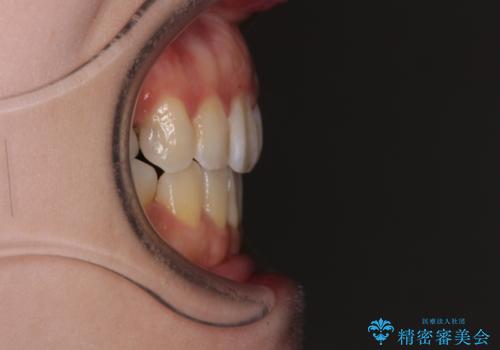

出っ歯と奥歯の欠損 ワイヤー矯正とインプラント治療

- 口元の突出感と奥歯の欠損を気にして来院された患者様です。

口元の突出感改善には、上下左右の第一小臼歯4本を抜歯し、奥歯の欠損部には矯正治療の途中でインプランを埋入していくこととしました。